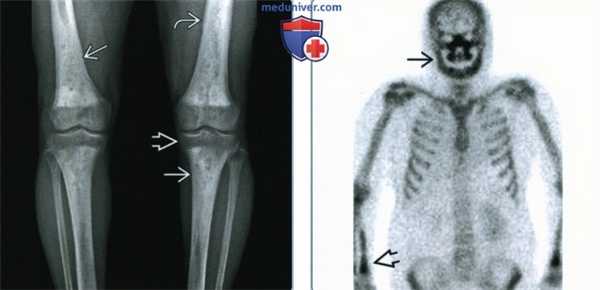

(Слева) Рентгенография в ПЗ проекции: определяются склеротичные огрубевшие трабекулы с литическими областями в диафизах длинных трубчатых костей. Склероз приводит к сужению костномозгового канала и отсутствию четкой границы между каналом и кортикальным веществом. Изменения симметричны, эпифизы не поражены. Волнистость кортикального вещества говорит о поражении надкостницы.

(Справа) Сканирование костей скелета, прямая проекция: у этого же пациента определяется поражение дистального отдела лучевой кости и костей лицевого черепа; осевой скелет не поражен. Картина характерна для болезни Эрдгейма-Честера. (ЭЧ). (Слева) МРТ Т1ВИ, корональный срез: у пациента 79 лет определяются пятнистые области ↓ ИС, замещающие нормальный желтый костный мозг в диафизах, и однородная область ↓ ИС в дистальном метадиафизе. В дистальных эпифизах бедренный костей желтый костный мозг не изменен.

(Справа) Сканирование костей скелета, прямая проекция: у этого же пациента определяется поражение дистального отдела лучевой кости и костей лицевого черепа; осевой скелет не поражен. Картина характерна для болезни Эрдгейма-Честера. (ЭЧ).